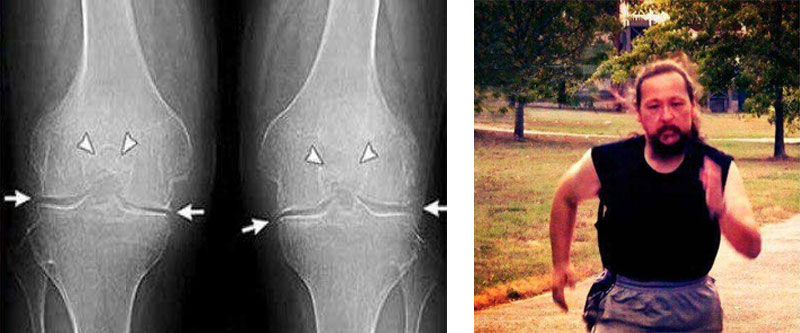

Εμένα το Turmeric Curcumin με βοήθησε πολύ! Πρήστηκε το γόνατο δεν μπορούσα να λυγίσω το πόδι μου. Ο πατέρας μου μου έφερε από κάπου το και Turmeric Curcumin Δόξα το Θεό! Δείτε την διαφορά:

Εμένα το Turmeric Curcuminμε βοήθησε πολύ! Πρήστηκε το γόνατο δεν μπορούσα να λυγίσω το πόδι μου. Ο πατέρας μου μου έφερε από κάπου το και Turmeric Curcumin Δόξα το Θεό! Δείτε την διαφορά: